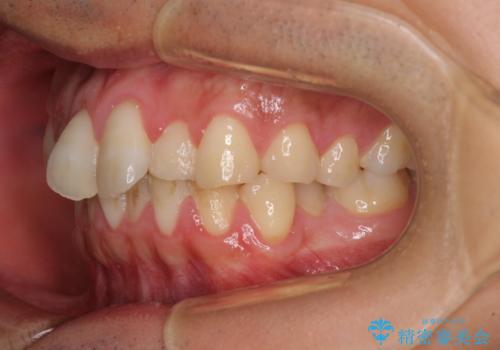

捻れて飛び出した前歯 インビザラインで整った前歯に

- 上下前歯のデコボコと、それに伴う出っ歯を気にして来院された患者様です。

インビザラインによる上下歯列の側方拡大と後方移動、IPR(歯と歯の間を削る)にるスペースの獲得により歯列を整えることとしました。

歯と歯の間を削ることでうまくスペースコントロールでき、また、毎日22時間以上しっかりとマウスピースを装着していただいたので、スムーズに治療が進みました。